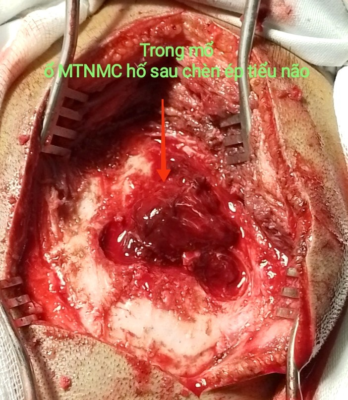

Hình 2. Hình ảnh đường vỡ xương chẩm, máu tụ trong mổ

Ca mổ diễn ra thuận lợi, lấy khối máu tụ, giải phóng chèn ép tiểu não. Kết quả Ctsccan sau mổ sạch máu tụ.